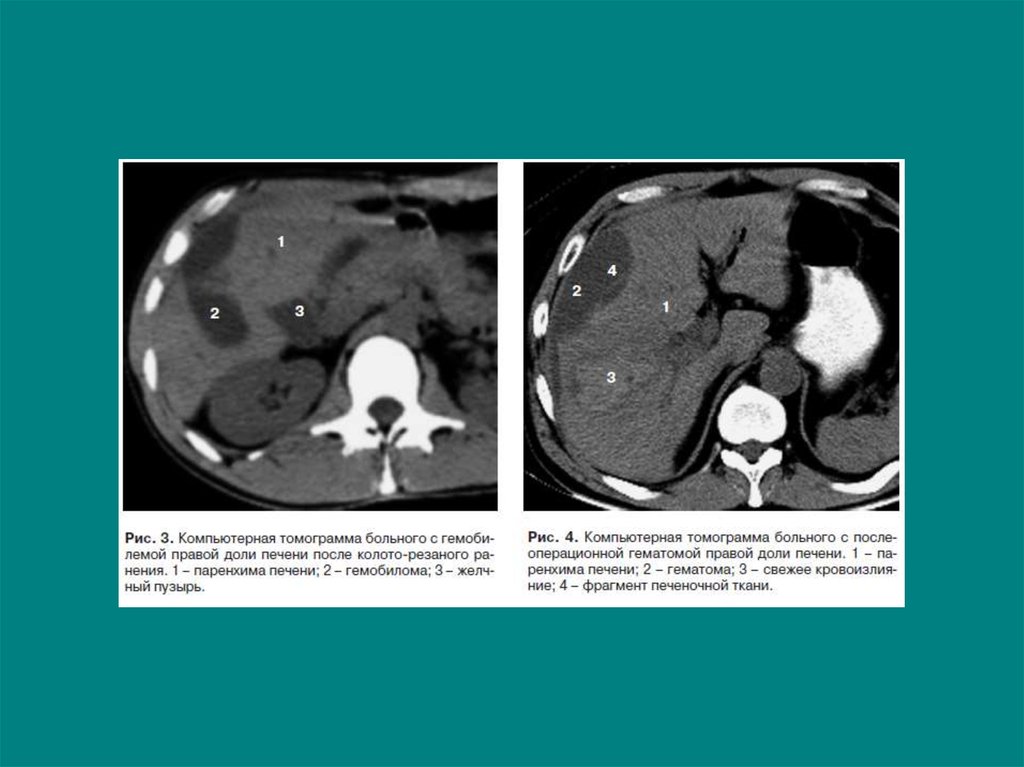

4. Травма печени

Центральная гематома печени (n=42)

5. Травма печени

6. Травма печени

Подкапсульная гематома печени (n=23)

7. Травма печени

Билома (билиогематома) печени (n=11)

8. Травма печени

Исследования в динамике (n=32)